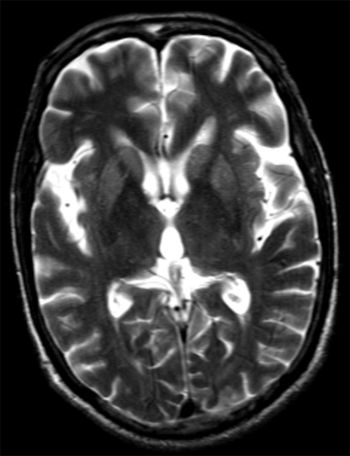

Creutzfeldt Jakob’s DiseaseByRozil Gandhi, DMRD, DNBOctober 22nd 2013Case History: A 70-year-old male, non-diabetic, non-hypertensive presented with acute history of sudden onset memory loss and hallucinations.